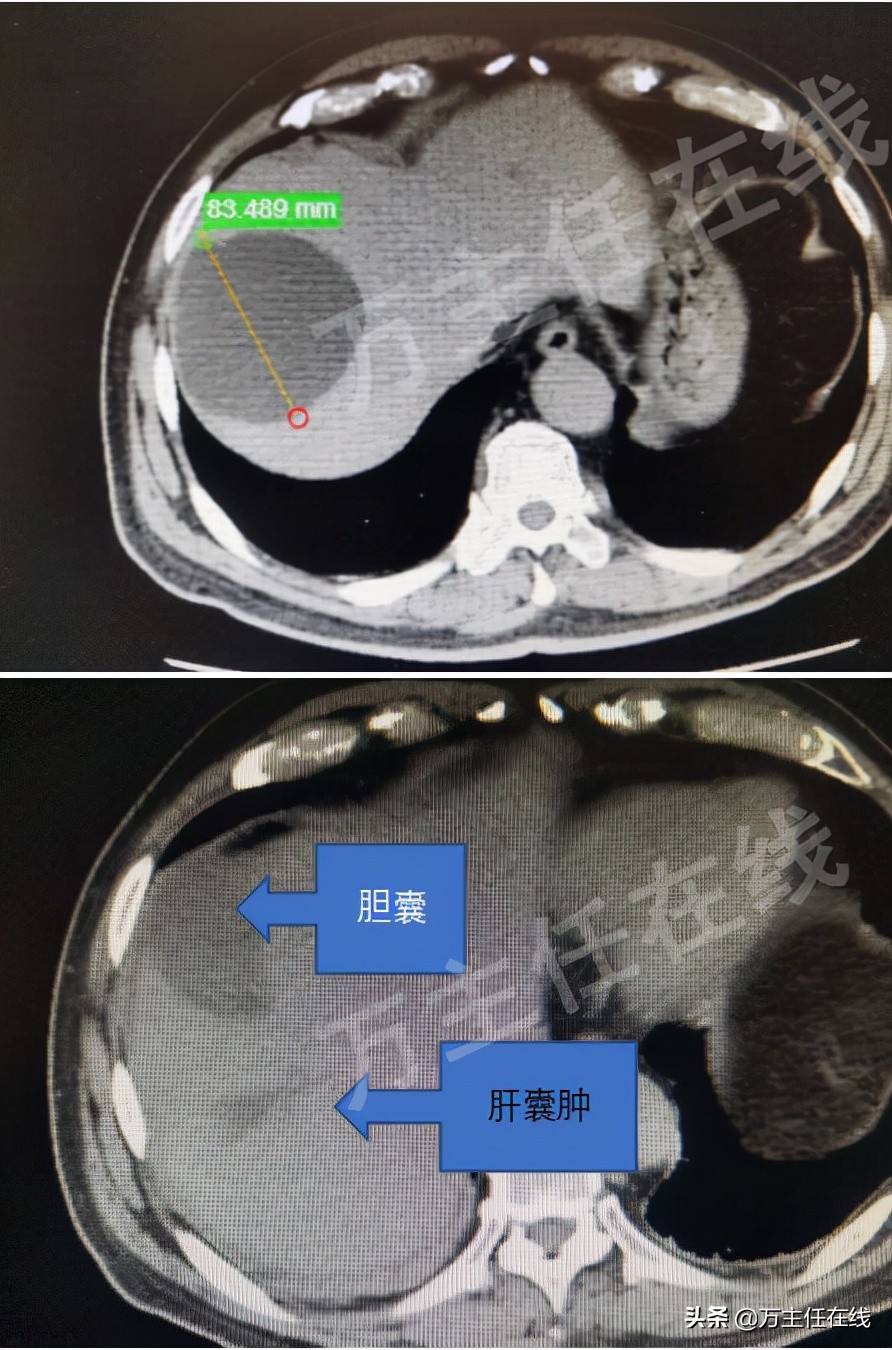

27日,万主任一早来到病房查房,辛奶奶已经恢复了肠道排气,没有腹痛等不适,万主任为辛奶奶开放了饮食,并安排了CT复查,结果显示肝囊肿几乎完全消失。紧接着,万任为辛奶奶安排了出院。这样,一个偌大的肝囊肿治疗,从入院到出院,还不到72小时。

肝囊肿治疗前后的CT表现